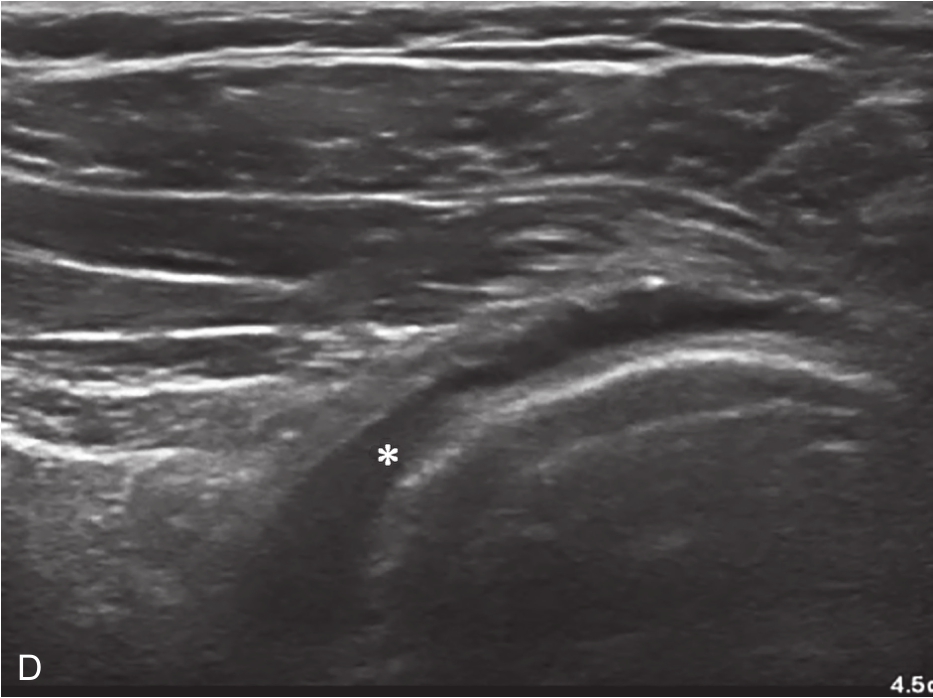

▲ 图2-6-4 超声引导下肩关节腔介入治疗超声图(二)

A.肩关节下关节囊增厚;B.超声引导下穿刺针进入盂肱关节腔

▲ 图 2-6-4(续)

C.超声引导下类固醇及生理盐水注射;D.注射治疗后关节腔扩张;双星号:增厚关节囊;箭头:穿刺针;单星号:关节腔